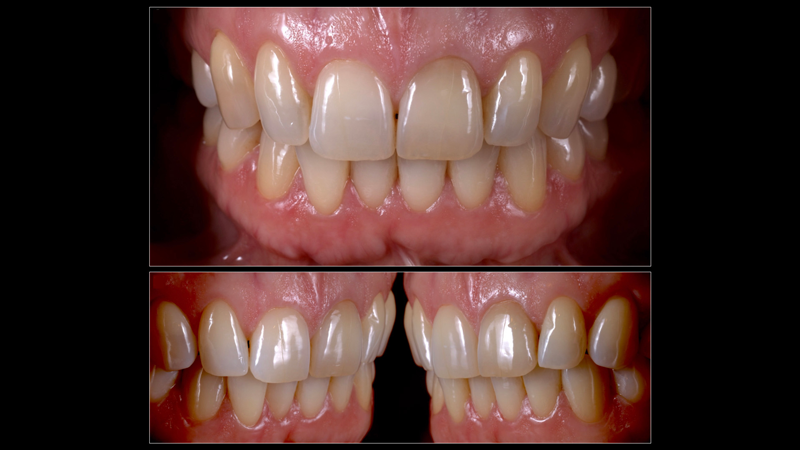

For clinical situations involving a nonvital and discolored natural tooth (Figure 10), intracoronal bleaching, also known as the "walking bleach" technique, has been consistently shown to be a conservative treatment option compared with more aggressive direct/indirect restorative procedures such as composite bonding, porcelain laminate veneers, or full coverage crowns.33Additionally, for patients requesting the lightening of a single dark tooth, internal bleaching is often more cost-effective and less dependent on patient compliance than the daily use of a whitening tray. Contemporary protocols often include the use of strong oxygen-releasing chemical compounds, such as 30% to 35% hydrogen peroxide, which have been associated with adverse complications including external invasive cervical root resorption.34,35 The evaluation and outcomes of endodontic techniques utilizing a safer 10% carbamide peroxide formulation are well-documented in the literature and clinically, and have proved to be a reliable, predictable option for the internal bleaching of nonvital discolored teeth (Figure 11).36-38

Fig 10. Discoloration of a nonvital single central incisor is a common clinical situation that can be addressed through a safe and conservative approach utilizing an internal bleaching technique (the “walking bleach” technique) with 10% carbamide peroxide (Pola Night, SDI).

Figure 10